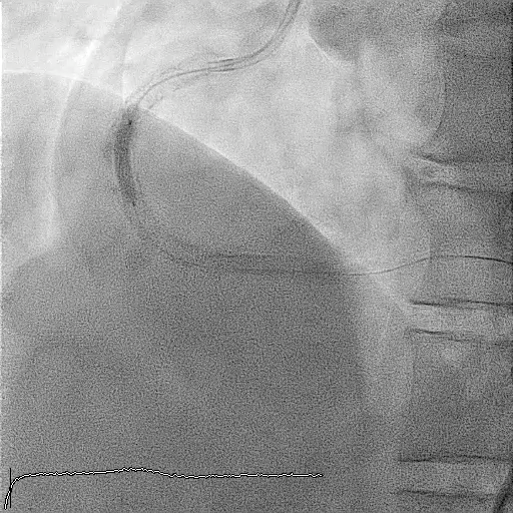

Subsequent coronary angiography identified a pseudoaneurysm in the right coronary artery (RCA), without any evidence of extravasation.

In this coronary catheterization procedure, a guidewire was used to cross the lesion and advanced to the posterolateral branch (PL). An intravascular ultrasound (IVUS) examination was conducted, revealing a pseudoaneurysm in the mid-right coronary artery (m-RCA). To cover the pseudoaneurysm, a 3.5 x 16 mm cover stent was deployed in the m-RCA at a pressure of 16-18 atmospheres for 15-20 seconds, repeated twice. Subsequently, the cover stent was further post-dilated with a 3.75 x 15 mm non-compliance balloon at 18-20 atmospheres for 10 seconds, also performed twice. Optical coherence tomography (OCT) was then performed, showing a post-dilation stent MSA of 7.40 mm² with good apposition and expansion. The cover stent was additionally dilated with a 4.0 x 30 mm drug-eluting balloon (DEB) at 6 atmospheres for 60 seconds. The final angiography demonstrated TIMI grade 3 flow without any extravasation.

Case Summary

Post-intervention angiography demonstrated improved blood flow in the affected artery. The RCA pseudoaneurysm was effectively sealed, and subsequent imaging confirmed appropriate stent placement. The use of IVUS and OCT allowed for optimal sizing and placement, leading to a successful outcome.